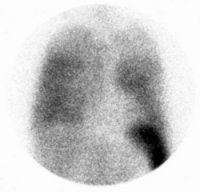

Non-specific diffuse lung uptake: Diffuse lung activity can be seen in this asymptomatic patient. Diffuse lung activity is uncommonly associated with infection. |